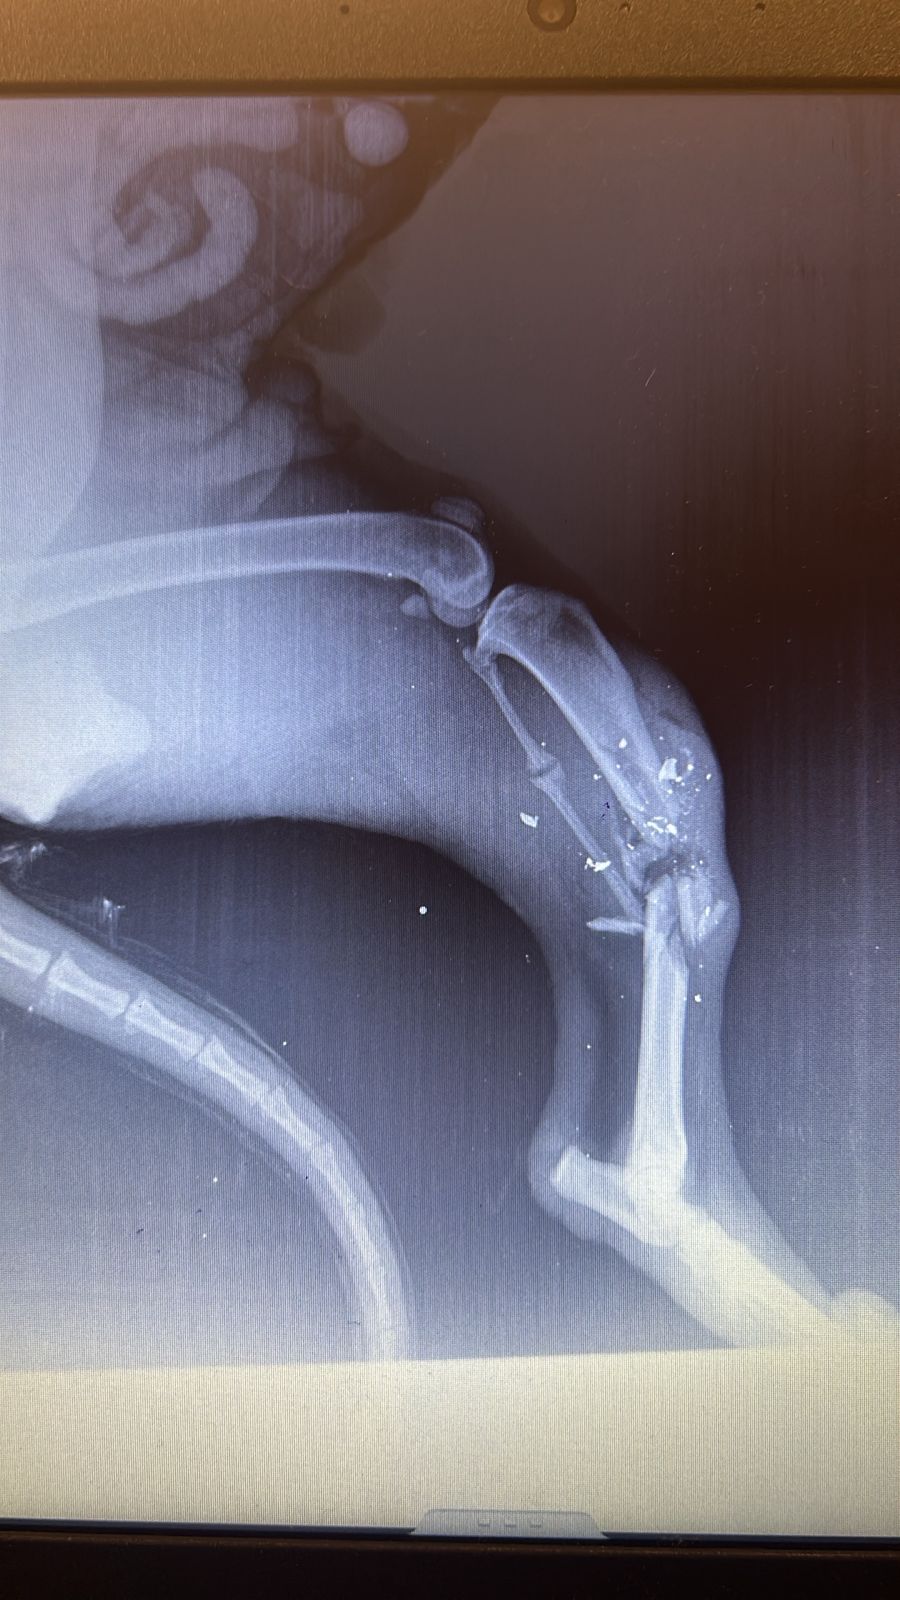

Peaches was rescued from Ramlet el Bayda. She was shot by an official from the municipality. Her leg was completely shattered. We had to amputate! She’s very mellow, sweet and is good with other dogs. DOB: 8/8/2017